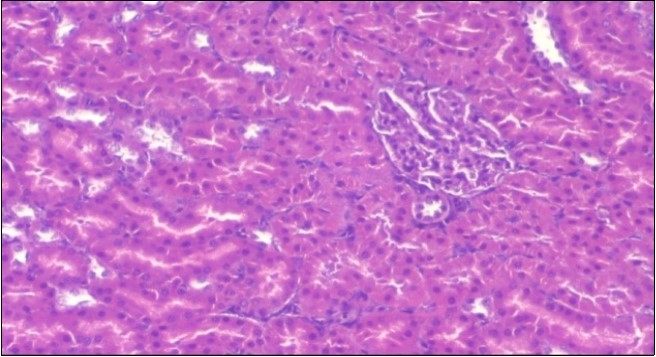

Effect of Ator, Fennel and Their Combination on the Liver of Obese Rats

The histological examination of the livers of control rats feeding standard diet showed normal architecture hepatocytes, blood sinusoid and central vein, figure 6. The rats which were fed on a (HFD), showed swollen hepatocytes with vacuolated cytoplasm filled with fatty infiltration, congested central vein and disappearance of blood sinusoids, figure 7. By comparison, the liver of rats that were treated by fennel after obesity and control mice observed nearly normal of the hepatocytes with eosinophilic cytoplasm, central vein and clear blood sinusoids and more bi-nucleated cells, figure 8. While examination of rats' liver that were treated by Ator and after the obesity appears, they showed mild fatty change in hepatocytes, few hepatocytes retain is eosinophilic cytoplasm and central vein figure 9. Liver of rats that were treated by fennel and Ator after obesity and control rats are showing nearly normal hepatocytes figure 10.

Figure 6.Photomicrogragh of liver section of control rat showing normal architecture Hepatocytes, blood sinusoid and central vein, (H&E) (40X).

Photomicrogragh of liver section of control rat showing normal architecture Hepatocytes, blood sinusoid and central vein, (H&E) (40X).